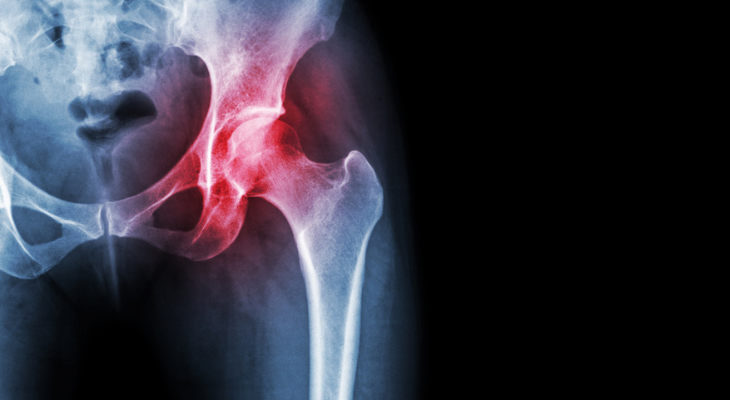

Osteoarthritis not only causes pain, but also makes it difficult to do a variety of everyday things. When your joints are stiff and achy, climbing stairs, buttoning your shirt, or getting in and out of the bathtub without falling become more challenging than you could ever have imagined. Adding chiropractic care to your osteoarthritis treatment plan can reduce both pain and stiffness.

- Keep Pain Under Control. Osteoarthritis happens when the cartilage at the ends of the bones in a joint wears away. Without that protective cushioning, the bones grind together every time you move the joint, causing jolts of pain. Chiropractic adjustments realign your joints and reduce painful pressure on the bones and cartilage. Self-reported pain levels in patients who had osteoarthritis of the neck decreased from 8.6 to 2.6 after receiving manipulation (adjustments) and mechanical mobilization device therapy, according to a research study published in the Journal of Manipulative and Physiological Therapeutics.

- Decrease Inflammation. Joint inflammation, a key factor in both pain and stiffness, is more likely to occur when your joints are misaligned. When misalignments are corrected, inflammation improves.